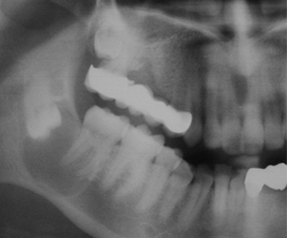

ÇENE KİSTLERİ